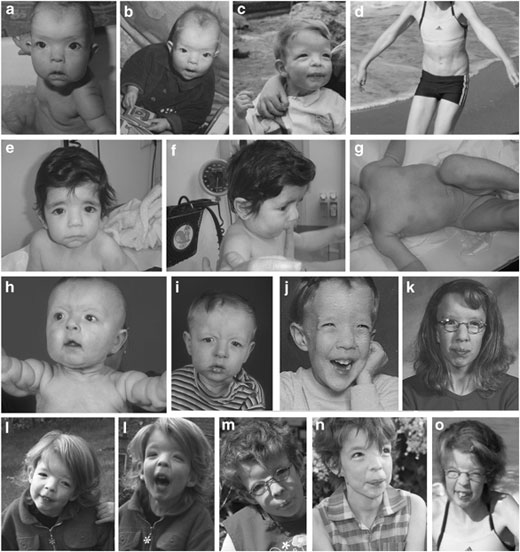

Dermatología | Enfermedades raras

La Cutis Laxa (CL)

La cutis laxa (CL) es una afectación hereditaria o adquirida del tejido conectivo. Se caracteriza por una piel arrugada, abundante y flácida, que ha perdido su elasticidad, y se asocia con anomalías esqueléticas o del desarrollo y, en algunos casos, con una afectación sistémica grave. No existe un tratamiento eficaz para la CL y el manejo es sintomático.

Se caracteriza por una piel arrugada, abundante y flácida, que ha perdido su elasticidad, y se asocia con anomalías esqueléticas o del desarrollo y, en algunos casos, con una afectación sistémica grave.

La mayoría de los casos de CL son hereditarios. Su prevalencia al nacimiento se estima en 1/1.000.000 y hasta el momento, sólo se han descrito unas 200 familias en la literatura.

Se han descrito numerosas variantes de CL, que se diferencian según el modo de transmisión hereditario, la extensión de la afectación visceral, las anomalías asociadas y la gravedad de la enfermedad.

Las formas autosómicas recesivas de CL (ARCL) parecen ser las más frecuentes, habiendose descrito dos subtipos: ARCL1 y ARCL2.

La ARCL1 es la forma más grave, con una afectación generalizada que puede ocasionar complicaciones que condicionan el pronóstico vital (enfisema pulmonar y atelectesias, anomalías vasculares, y devertículos en el tracto gastrointestinal y genitourinario).

La ARCL2 incluye un espectro de enfermedades de gravedad variable, desde el síndrome de la piel arrugada, hasta procesos más graves asociados a retraso del crecimiento, anomalías del desarrollo y esqueléticas (ARCL2 clásica, tipo Debré).

El síndrome de De Barsy y la gerodermia osteodisplástica pueden presentan un importante solapamiento clínico con la ARCL2.

El síndrome del cuerno occipital (cutis laxa ligada al X (XRCL) es muy parecido a la ARCL2; aunque algunos pacientes presentan un fenotipo más grave y afectación sistémica.

La CL autosómica dominante (ADCL) suele manifestarse por una afectación leve, aunque se han descrito algunos casos con manifestaciones sistémicas (hernias, anomalías valvulares cardíacas, manifestaciones cardiovasculares, divertículos gastrointestinales y enfisema).

El pronóstico es variable: desde una evolución fatal en los niños afectados de ARCL1 hasta una esperanza de vida normal en las formas menos graves.